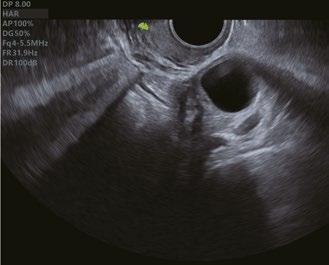

Vierkammer Ansicht